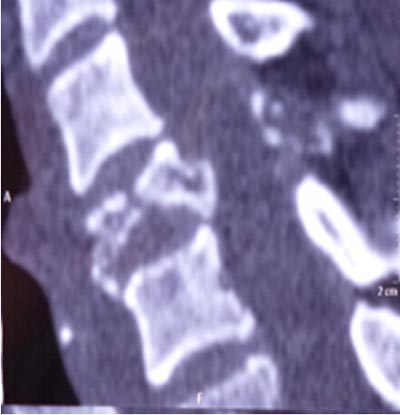

近日,我院骨二科成功完成一例前后联合入路颈椎肿瘤切除重建术。该患者来自陕西汉阴,女,45岁,1月前无明显诱因感颈肩部疼痛不适,在当地医院就诊行相关检查诊断:“颈5椎体病理性骨折”,考虑手术的风险及难度极高,建议转至我院。磁共振检查示“颈5椎体及附件破坏并塌陷”,椎动脉血管造影示“右侧椎动脉发育不良,颈5椎体及附加破坏并包绕椎动脉”。积极术前准备工作,全科讨论后制定前后联合入路肿瘤切除重建手术方案。手术于2014.10.20日如期进行,张晓琴教授负责麻醉,术中进行动脉血压监测、中心静脉压监测、动态血气分析、全面的的生命体征监测,确保了手术安全和平稳。手术由李浩鹏教授指导,王栋副教授主刀,赵波主治医师协助。先取颈部前侧入路,于气管鞘及食管鞘间隙进入,切除颈5椎体,术中可见颈5椎体破坏,彻底切除病变组织至双侧横突,显露椎动脉及神经根,小心完整切除右侧椎动脉包绕的鱼肉样病变组织,更换手套,取左侧髂骨修剪为颗粒状及短棒状置入钛网放置于颈5椎体缺损部,前方钛板固定进行重建。再取俯卧位,颈部后正中切口,彻底切除颈5棘突及双侧椎板至双侧横突,双侧侧块钢板固定。手术顺利,术前症状显著改善,术后第二天即可在颈托保护下下地活动。该部位解剖复杂,血管、神经多,不易分离,有可能损伤椎动脉,脊髓及神经根,引起截瘫、大出血,脑坏死等,风险很大。术中以最精准的操作,解剖性、根治性切除病灶,同时进行了骨性重建,保证了颈椎的稳定性。该肿瘤的成功切除及重建,显现了我院骨二科的综合技术实力,以及团结协作、严谨求实、不断进取的专业精神,也标志着我院的脊柱外科达到国内先进水平。